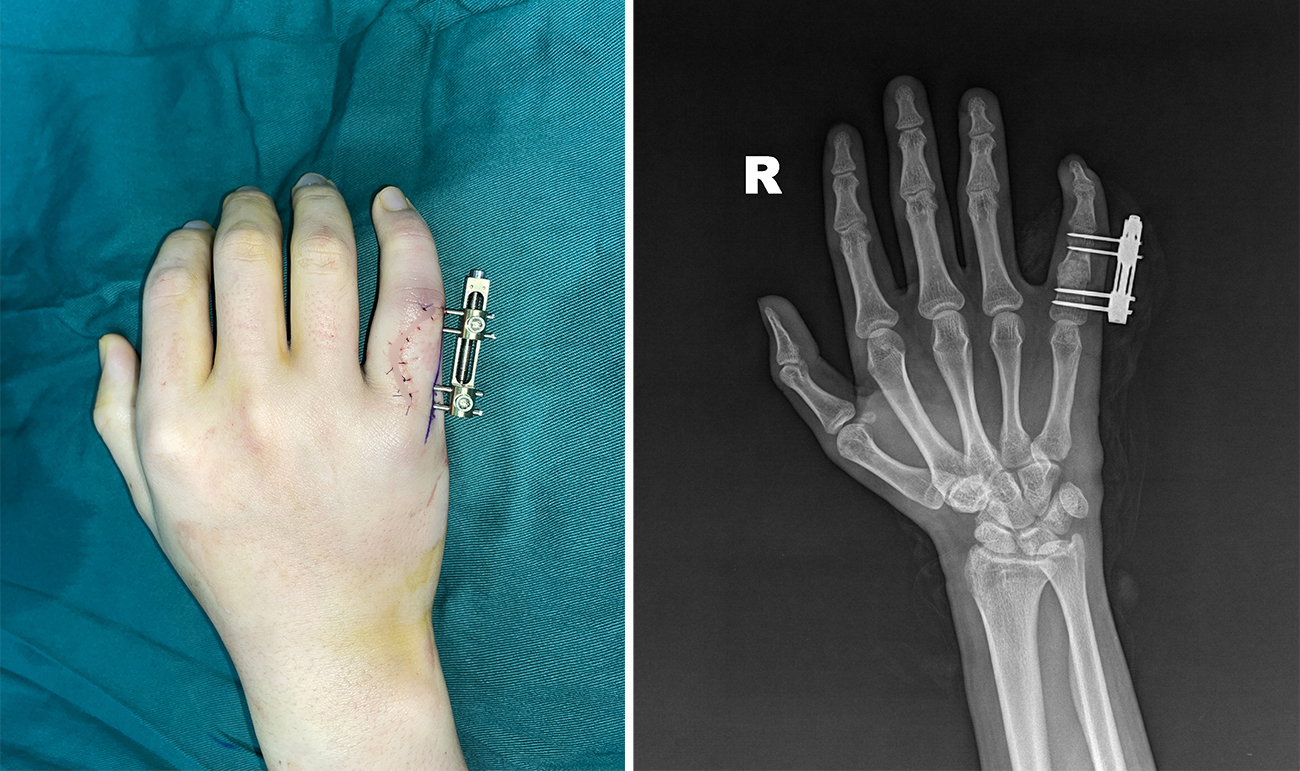

基于精准诊断与治疗关键点分析,手显微外科医疗团队为小李制定了个性化手术方案,由功能重建组组长李发祥主刀实施手术。术中,先用Mini外支架进行固定,保证骨折的对合及力线,然后精准清理骨折断端及软骨瘤病灶,彻底去除病变组织,再取髂骨进行植骨,精准填补骨缺损,全程历时1小时,手术顺利完成。

(▲术中,安装Mini外支架)

对于这类病理性骨折,传统治疗方案多采用克氏针或钢板内固定,而重庆长城骨科医院手显微外科则优先采用Mini外支架技术。李发祥医生解释:“Mini外支架的核心优势正是破解此类疾病诊疗难点的关键:不剥离骨膜,有效保护骨折端血运,为植骨愈合提供良好环境;外支架固定牢固,不用打石膏,且位于体外,避免对肌腱和关节囊造成干扰,让患者术后可尽早开展手指功能锻炼,从根源上预防关节僵硬和肌腱粘连;同时无需二次手术取内固定,大幅减少患者创伤,缩短恢复周期。这些特点对于手部功能恢复至关重要——手指的活动能力,直接决定了手的使用价值。”

手指恢复如初,功能重建为手足四肢护航

术后,医疗团队为小李严格执行伤口换药、抗感染等对症治疗措施,密切监测伤口愈合进度及小指末梢血运情况,确保术后恢复平稳。期间复查DR显示,骨折断端复位良好,固定牢固,植骨区骨密度均匀、填充充分,各项指标均符合预期恢复标准,经过7天的规范诊疗与护理,小李顺利出院。

8周左右,小李返院复查并拆除了Mini外支架。经李发祥医生专业评估,其小指抓握动作灵活、肌力恢复理想,已达到正常生理功能水平。作为青少年学生,小指的精细活动能力与抓握力量直接影响握笔书写、日常抓持及体育活动,此次功能的全面恢复,让小李得以摆脱伤病困扰,顺利回归正常校园生活。